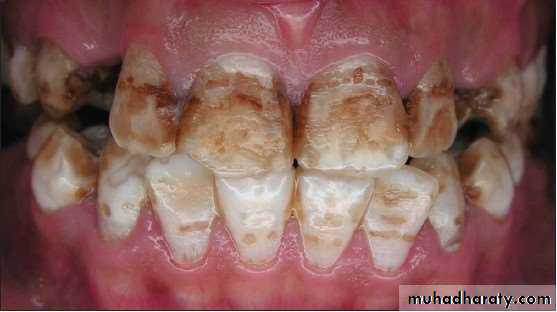

SEVERE (4) All enamel surfaces

of the tooth are affected andhypoplasia is so marked that the

general form of the tooth may be

affected. The major diagnostic

sign of this classification is

discrete or confluent pitting.

Brown stains are widespread

and teeth often present a

corroded-like appearance.